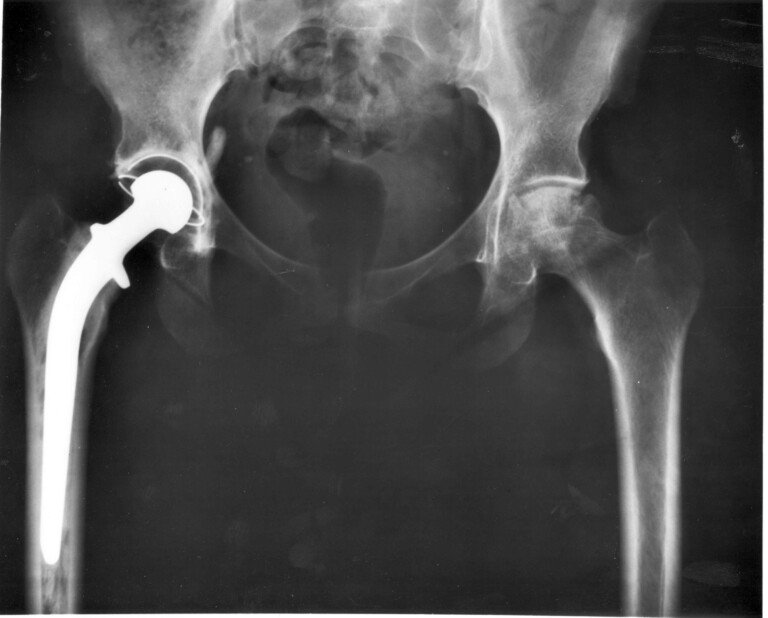

Mobility After Hip Replacement What to Expect and How to Adapt During Recovery Best Pain In Bum Cheek After Hip Replacement learn about the common types of pain after hip replacement surgery, such as thigh, knee, buttock and shin pain, and how to manage them. Pain typically increases with movement of the leg out to the side and with activities that require stabilization of the pelvis, especially single leg movements. the pain does not render you immobile and does. Pain In Bum Cheek After Hip Replacement.